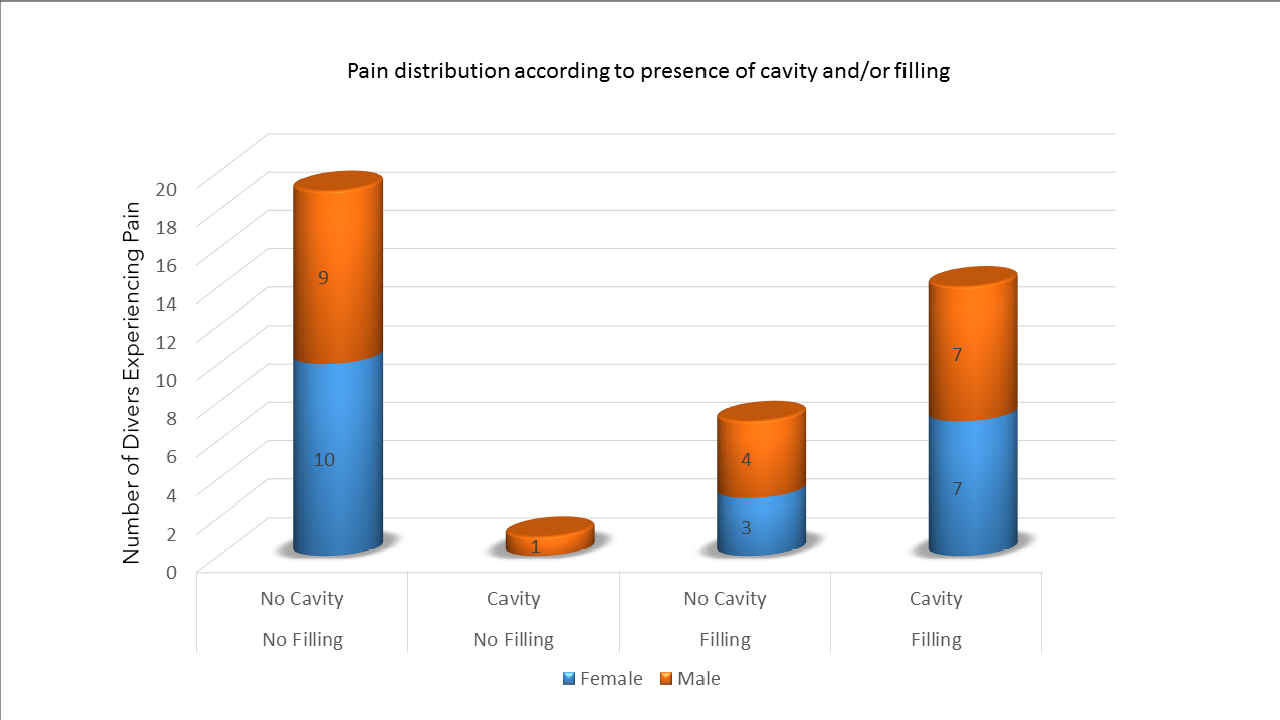

The research found that 41 percent of divers experienced dental symptoms in the water, from tooth squeeze to jaw pain – factors that could severely affect the entire diving experience, and even force some to abort the dive.

“Of the divers that participated in this study, 42 percent reported tooth squeeze (barodontalgia) as the type of problem, 24 percent experienced pain from holding the regulator too tightly, 22 percent reported jaw pain, five percent noted loosening of crowns placed on teeth, five percent reported pain in the gums, and two percent reported a broken dental filling.”